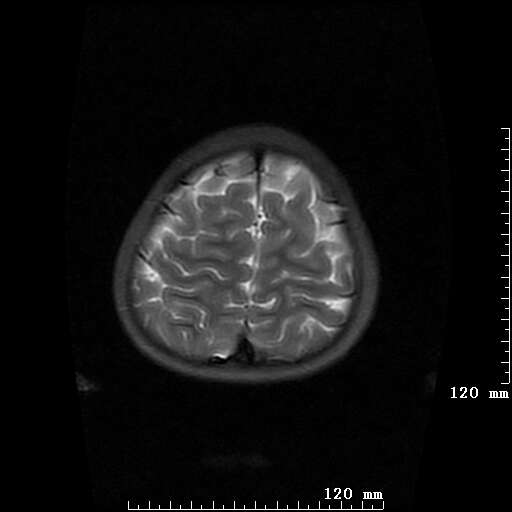

女,7岁,三岁才说话、走路。现智力尚可,走路不稳。临床怀疑大脑发育不全。

考虑 脑白质发育不良

脑折质变薄,双侧侧脑室稍扩张,支持考虑脑折质发育不良

侧脑室周围白质软化症。

考虑胼胝体发育不全,髓鞘形成不良。

支持考虑胼胝体发育不全,髓鞘形成不良。

脑裂畸形伴灰质异位

侧脑室周围白质数量减少,侧脑室不对称性扩大,左侧侧脑室后角呈方形改变,脑沟加深,结合临床考虑脑室周围白质软化症(pvl)。期待结果!

只看出灰质异位

支持脑白质发育不良。